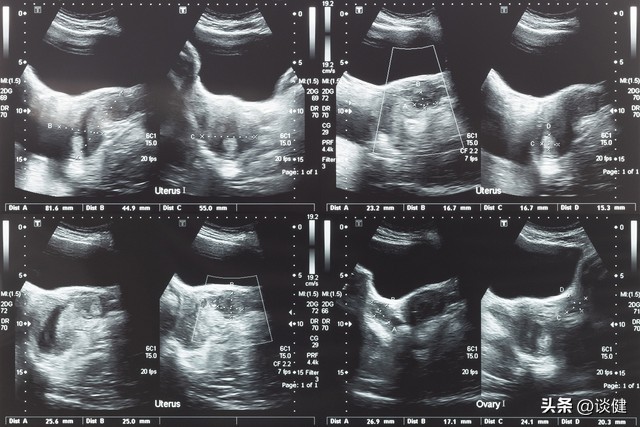

国际妇产科组织(FIGO) 根据肌瘤的详细解剖位置订定了一个分类系统(如下图所示),将子宫肌瘤分成10类;如此对于月经异常出血,或是不孕甚至反复流产的临床处理会更有帮助。